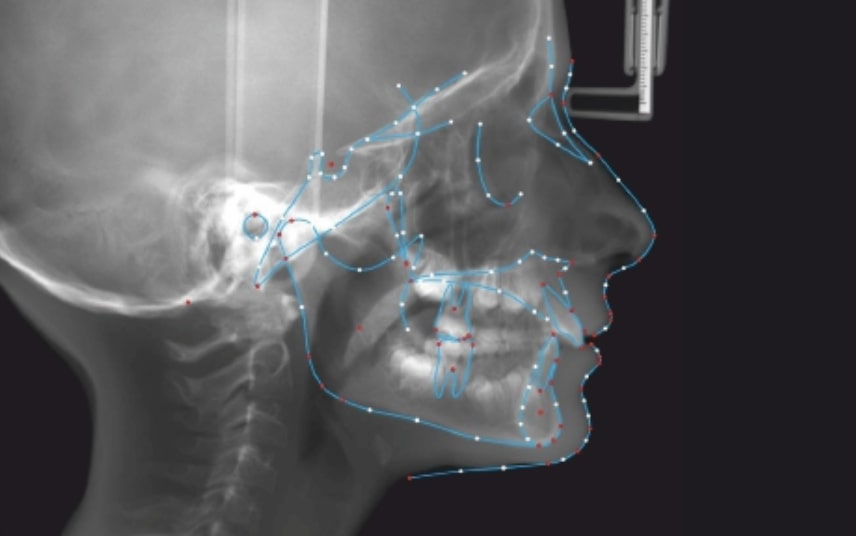

Clinical examination and diagnosis

SKELETAL PATERN: Class 2

DENTAL:

- Molar and Canine class 2 on the right side – Molar and Canine clss 1 on the left side

- Upper diastema (11-21)

- Increased Overjet

- DeepBite

- Reduced Transversal Diameters

- Deviated Lower Midline 2 mm to the Right